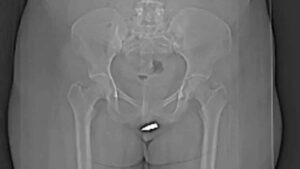

Las imágenes de la lesión fueron publicadas en el informe, la radiografía muestra que la bala se alojó en el clítoris y los médicos dijeron que nunca habían visto un caso así.